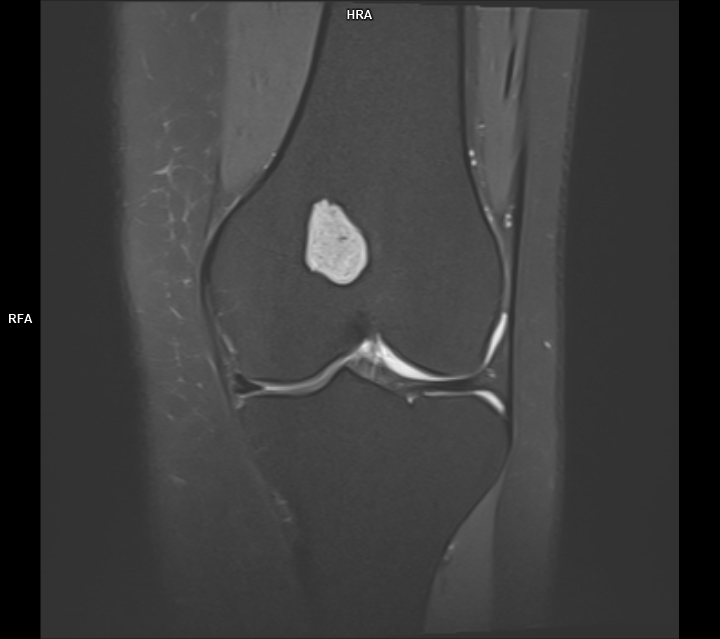

CAZ nr 44 Encondrom femural distal

Figura 2: achiziție în plan sagital în ponderație PD cu saturația grăsimii

Discuție caz nr 44: Encondromul este o tumora benignă cu origine cartilaginoasă; cazul prezentat evidențiază o leziune net delimitată în hipersemnal PD, hiposemnal T1, fără restricție de difuzie, ce nu modifica semnalul țesutului osos de vecinătate si se dezvoltă de o parte şi de alta a cartilajului de creștere.